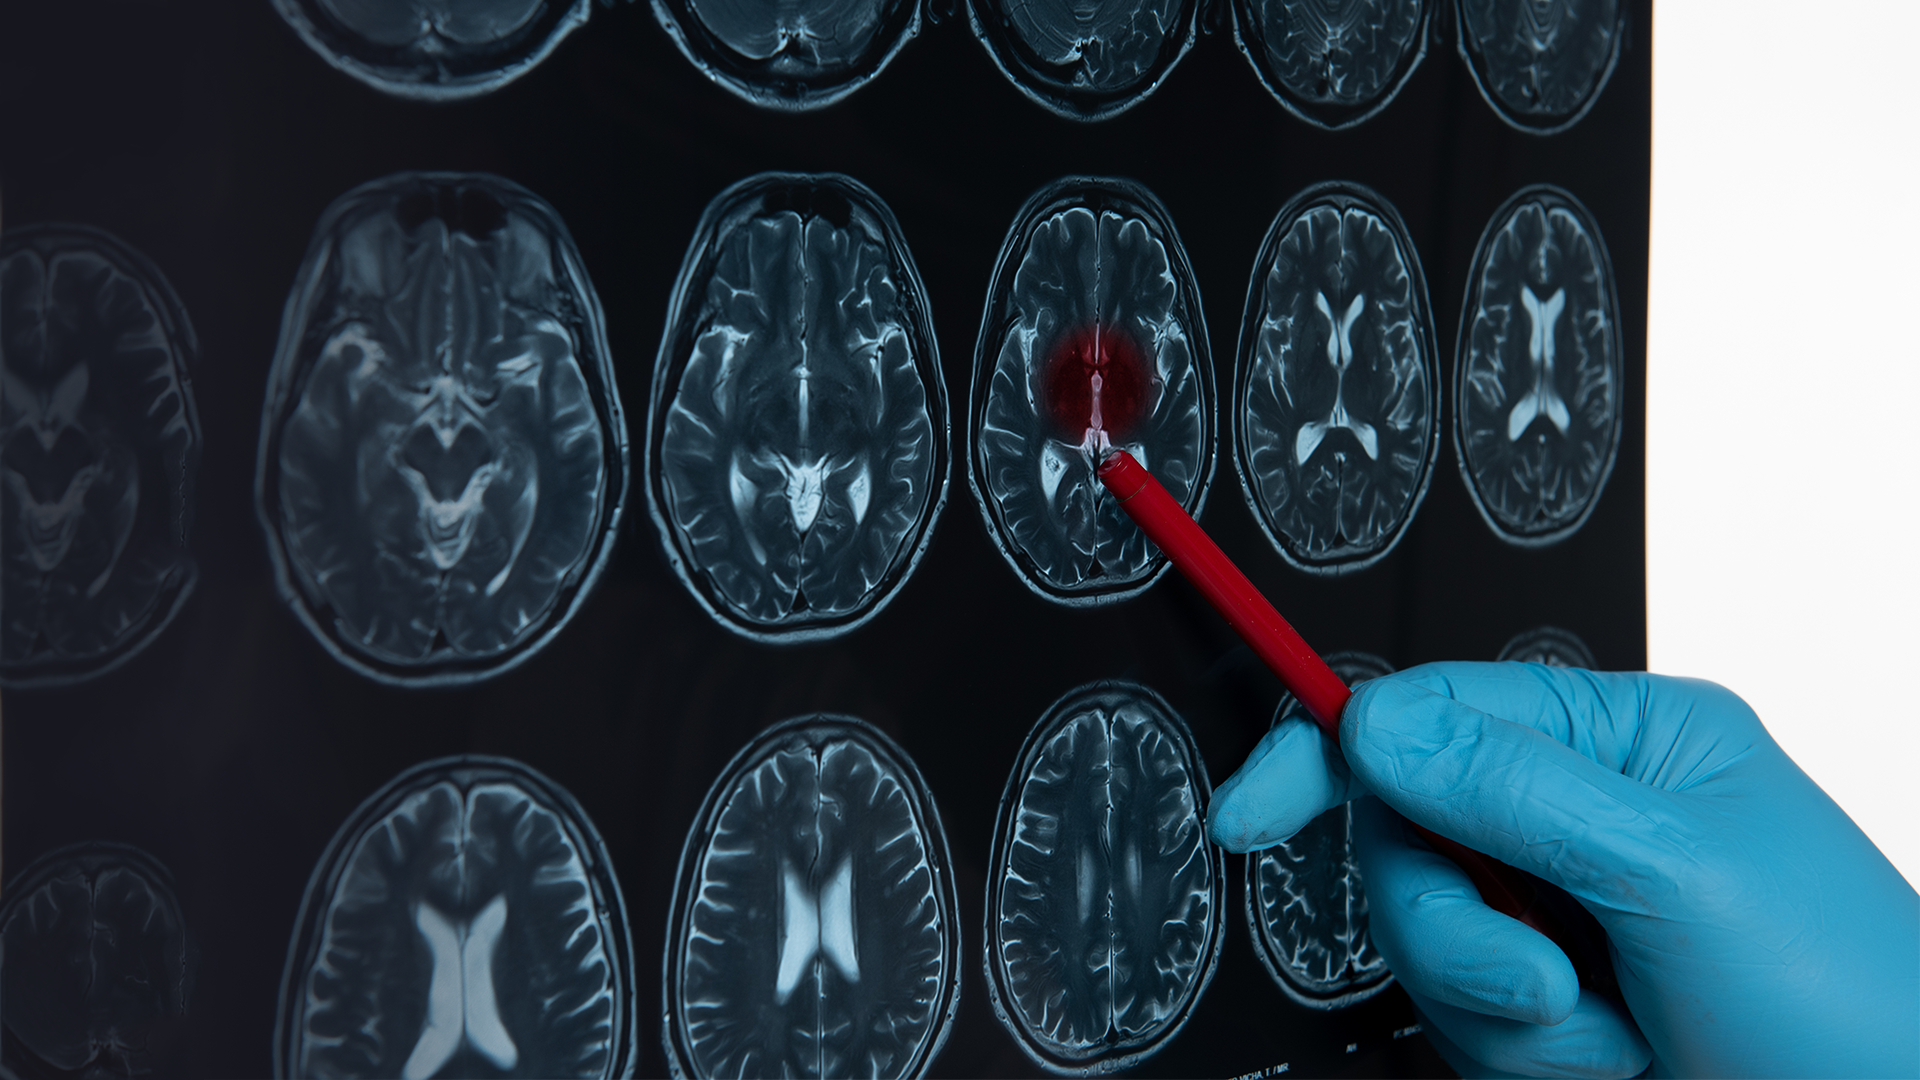

After a thorough examination and MRI, Mr Mabunda was referred to Dr Stevens Hlahla, a neurosurgeon practising at Netcare Unitas Hospital.

“Pituitary adenomas are non-cancerous tumours, however the condition affects pituitary function and, if the tumour grows it can compress the optic nerve and the person can eventually go blind if it is not treated,” says Dr Hlahla, who harnesses minimally invasive endoscopic techniques to operate deep within the brain.

Pituitary adenomas, such as the one Mr Mabunda was diagnosed with, vary in size. A micro tumour can cause problems affecting the person’s hormones, and this can lead to issues such as hypertension and diabetes, and is strongly associated with Cushing’s disease, while larger tumours can cause complete blindness if not treated in time.

Larger tumours, like the one Mr Mabunda had, cause more than endocrine problems such as diabetes; they can also damage a person’s vision. “The majority of people are nearly blind by the time they present to me. Often, they have had symptoms for a long time, but previously, open brain surgery was the only option, or they were told their tumour was inoperable because it was too deep in the brain. Tragically, it’s frequently due to a lack of awareness that many suffer needlessly, simply because no one told them something can be done to help with this condition,” he says.